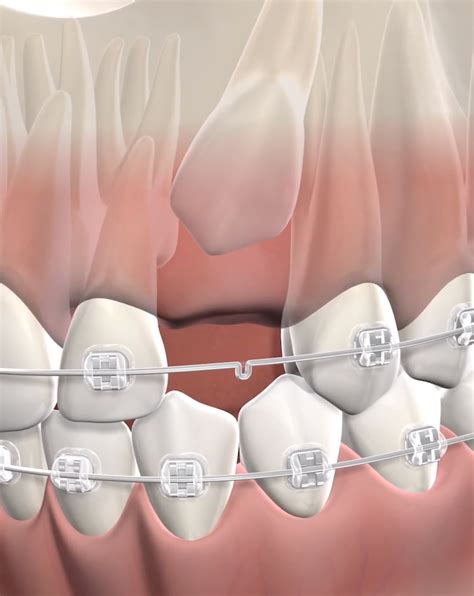

Orthodontic Traction Braces move the tooth into place. Patients who have undergone surgical exposure.

When the tooth is stuck in the bone, an oral surgeon performs an exposure procedure. This involves making a small incision in the gum to uncover the crown of the impacted canine tooth. Once the tooth is accessible, an orthodontic bracket and a small gold chain are typically attached to it. The orthodontist then uses this chain to apply gentle, continuous pressure, gradually guiding the tooth down into its designated space within the dental arch over several months.

It is important to understand that this is a gradual process. The speed of movement depends on the age of the patient and the complexity of the impaction. Adults often require a longer treatment duration than adolescents because the jawbone is fully developed and less pliable.

💡 Note: Proper oral hygiene during the traction phase is essential to prevent inflammation around the surgical site and the orthodontic attachments.